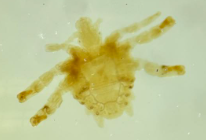

sarcoptes scabiei imago